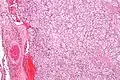

صورة مجهرية من ورم الجسم السباتي.

ويتم التعرف علي خلايا الورم بسهولة بواسطة الفحص المجهري. والخلايا السرطانية الفردية هي متعددة الأضلاع إلى بيضاوي ومرتبة في كريات خلوية مميزة تسمي (زيلابالن) (تعني بالانجليزية balls of cells (4) اي كرات من الخلايا). وتفصل هذه الكرات خلية ستروما زنثوما الليفية وتحيط بها خلايا داعمة.